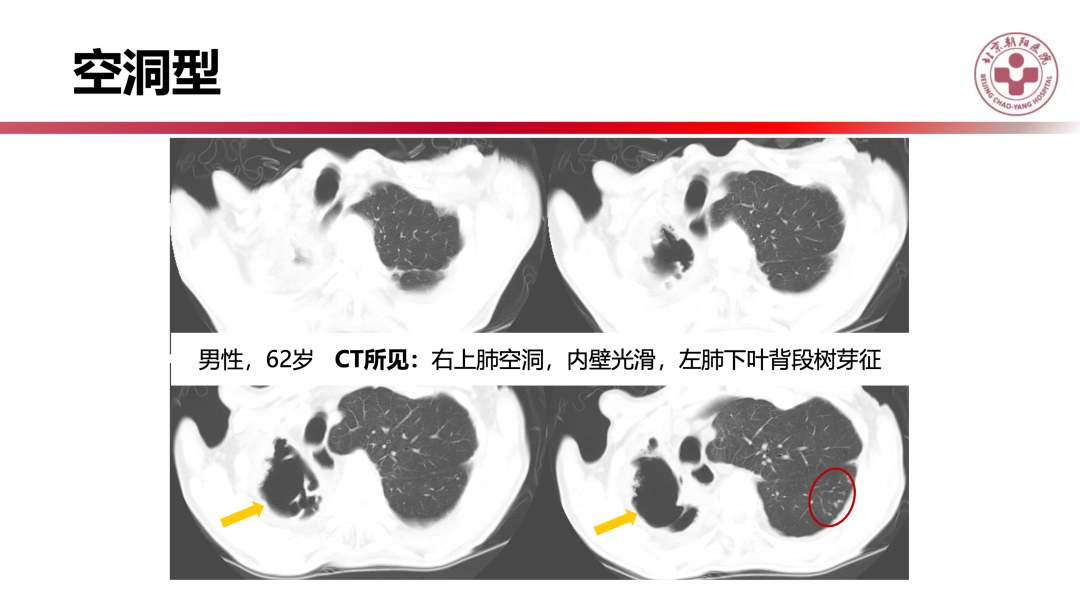

非结核分枝杆菌肺病有何影像学特点?|影像读片

来源 北京朝阳医院放射介入中心

课件提供 张子豪 翟晓力(放射)

点评专家 陈宁(放射)